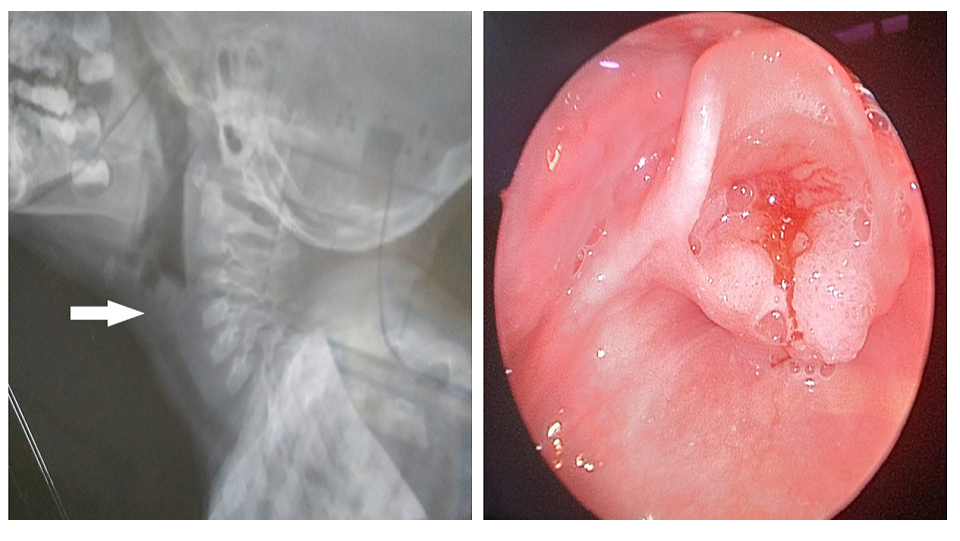

Anaesthetic Management of Emergency Tracheostomy in a Three Years Old Child with Recurrent Laryngeal Papillomatosis: A Case Report

Dr. Prakash Deb, Dr. Md. Yunus, Dr. Narendra Kumar Sharma

International Journal of Innovative Research in Medical Science·July 4, 2020